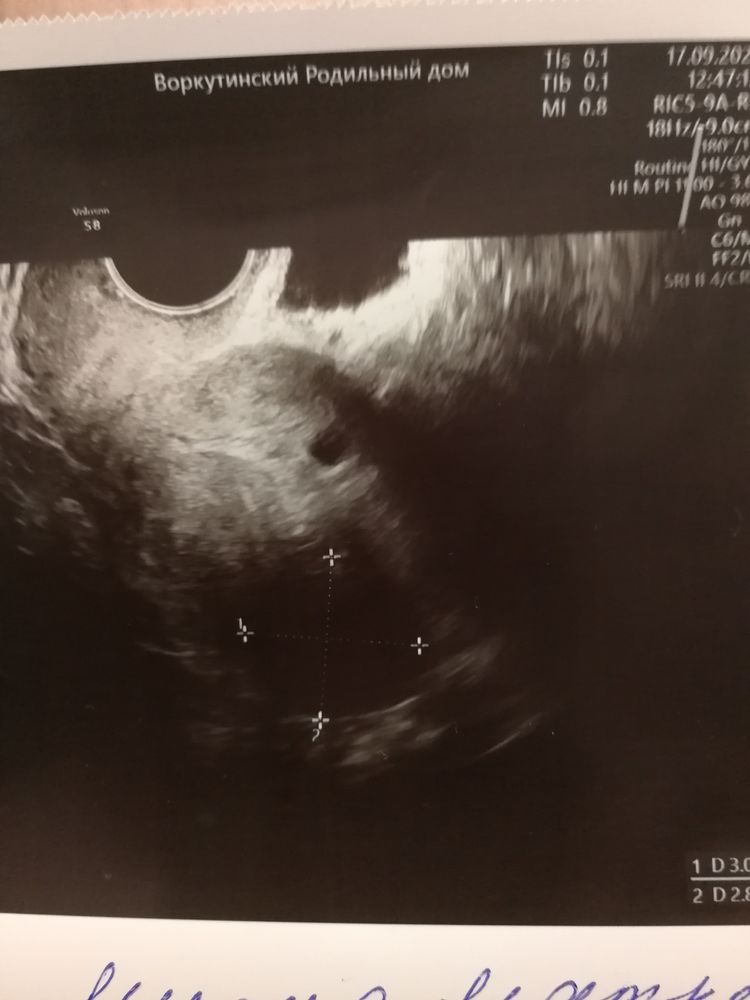

Жм вижу в пя,я бы через неделю пошла на УЗИ,а там и смотрела, отменить или нет прогестерон, сейчас бы принимала и да,узиста бы сменила

Сдайте хгч в динамике в местной лабе, ну хотя бы дважды. Утрик не отменяйте пока. И в ПЯ, что чуть больше, что то виднеется🙏🏻

Жди и переделывай. Мы,конечно, здесь можем ошибаться, но я почему-то тоже что-то вижу в ПЯ🤔

Мама мальчика (2 года) Санкт-Петербург

Не знаю, как вам, а я вижу два примерно одинаковых по размеру ПЯ. В вашем случае я бы переделала через неделю узи, так как если это двойня действительно, она может развиваться медленнее, чем одноплодная беременность. Ну и хгч бы сдать, понять, растёт или падает. Вообще если оно замерло на 5 неделе, уже бы мазало конкретно так даже на поддержке, если бы ЗБ была

Я вижу 2 одинаковых и одно малюсенькое, как точка...а с чего они взяли, что в процессе замирания? Не соответствует сроку или не растет?